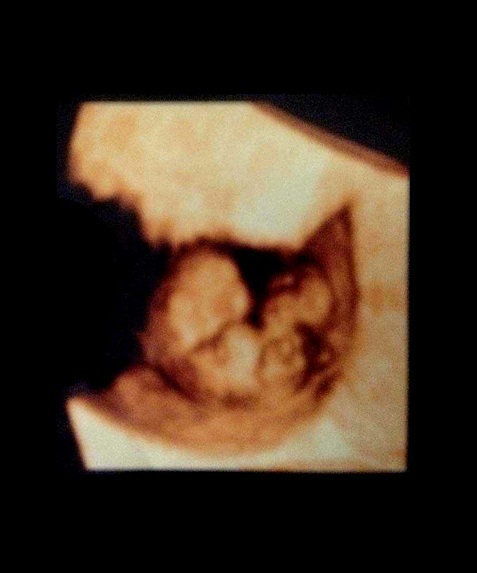

三维图

怀孕进入第7周了,这时的胚胎像一颗豆子,大约有13毫米长。现在如果你能看到自己的身体内部,你会发现胚胎已经有了一个与身体不成比例的大头。而且胚胎的面部器官十分明显,眼睛就像一个明显的黑点,鼻孔大开着,耳朵有些凹陷。

胚胎上伸出的幼芽将长成胳膊和腿,现在看上去已经很明显,手和脚看起来像小短桨一样。其它部分的成长包括垂体和肌肉纤维。现在你听不到胎心音,但是胚胎的心脏已经划分成左心房和右心室,并开始有规律的跳动,每分钟大约跳150下,比你心跳要快两倍。